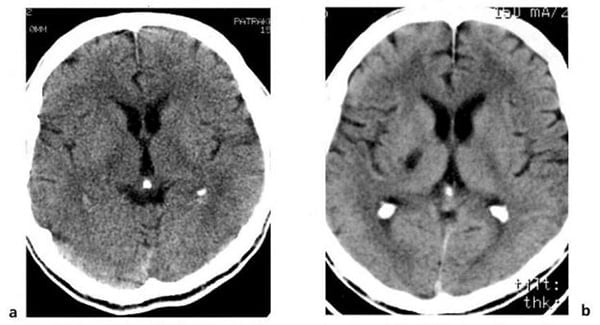

Hình 1.50. Phình mạch của động mạch não giữa, với máu tụ cũ nội sọ sau 4 tháng. Cùng bệnh nhân trong Hình 1.44. Trước tiêm (a), phình mạch có dạng mật độ cao nhỏ, máu tụ mãn tính mật độ thấp bao quanh (mũi tên). Sau tiêm (b), cho thấy phình mạch với huyết khối bán phần rõ hơn (mũi tên).